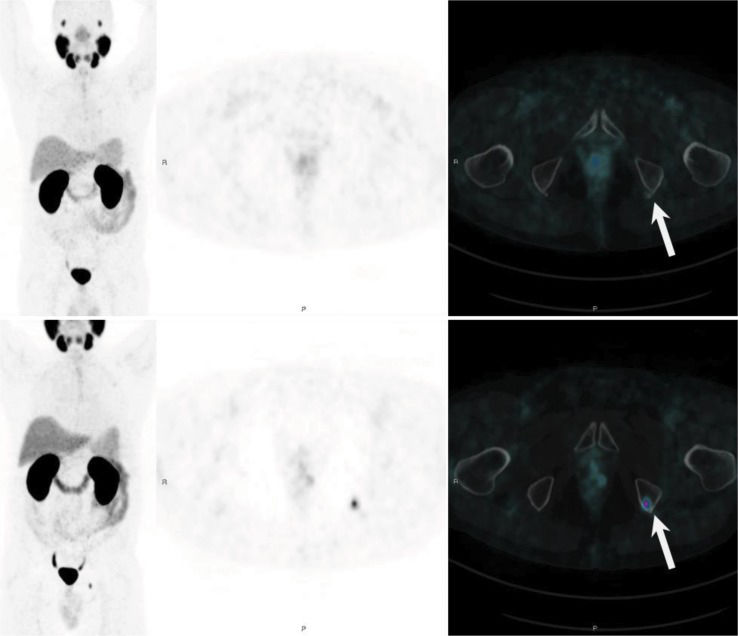

PSMA PET/CT has become the breakthrough imaging method for PCa relapse in the last 5 years 34. The literature has demonstrated that PSMA has better sensitivity and specificity than conventional methods or choline PET for detecting tumor recurrence, especially in patients with low PSA levels (<1.0 ng/mL) 35,36. The sensitivity rates of PSMA PET/CT according to PSA levels are 55-60% (0.2-0.5 ng/mL), 72-75% (0.5-1.0 ng/mL), 93% (1.0-2.0 ng/mL) and 97% (≥2.0 ng/mL). A recent study of PET/MR showed a higher detection rate in patients with very low PSA levels than those of other PET/CT studies in the literature, with detection rates of 44% (<0.2 ng/mL) and 72.7% (0.2-0.5 ng/mL) 37. These findings can be explained by the higher sensitivity of PET detectors in PET/MRI system and/or due to higher resolution imaging in the prostate bed. Clinical parameters that can influence also detection of BCR are high PSA levels (>1.0 ng/mL), short PSA doubling time (<6 months) and high Gleason score (≥8), all of which increase the detectability rate of BCR on PSMA PET 4,38 (Figure 2).

Evaluation of BCR in a 68-year-old patient treated with prostatectomy with a Gleason 7 adenocarcinoma (8 years) and prostate bed radiation (3 years), with a current PSA level of 0.29 ng/ml. 68Ga-PSMA-fused PET/MRI MIP images (A) demonstrated 2 pathologic areas of focal uptake in the pelvis (black arrows). Axial T2-weighted imaging (B) showed nonspecific bilateral hypointense tissue in the prostate bed (arrowheads); however, T1-weighted perfusion imaging (C) demonstrated hypervascularity in the left tissue (arrowhead), which also had focal PSMA uptake on fused PET/MR imaging (D), confirming local recurrence. Moreover, a 4-mm left external iliac lymph node (white arrow) was almost not visible on axial T2-weighted imaging (E) but had focal uptake on fused imaging (F), which was very suspicious for pelvic nodal recurrence.